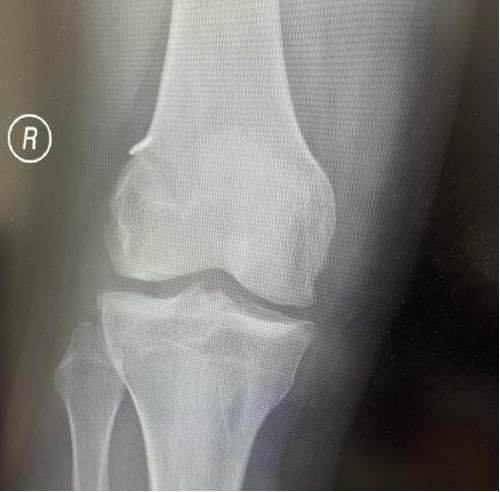

术后X线片

我院骨关节镜手术创伤小、恢复快,几位患者分别于术后5-7天好转出院。患者亲身感受膝关节快速康复过程,对科室医护表示感激,对早日回归正常的生活、工作及运动状态充满信心。

延安大学咸阳医院骨科三病区医护团队、通过精湛的手术技艺、优质的护理服务、早期科学的功能锻炼指导,都对患者的恢复起到极其重大的作用,我们骨科团队始终关注每一位患者的康复情况,为患者的运动健康保驾护航。